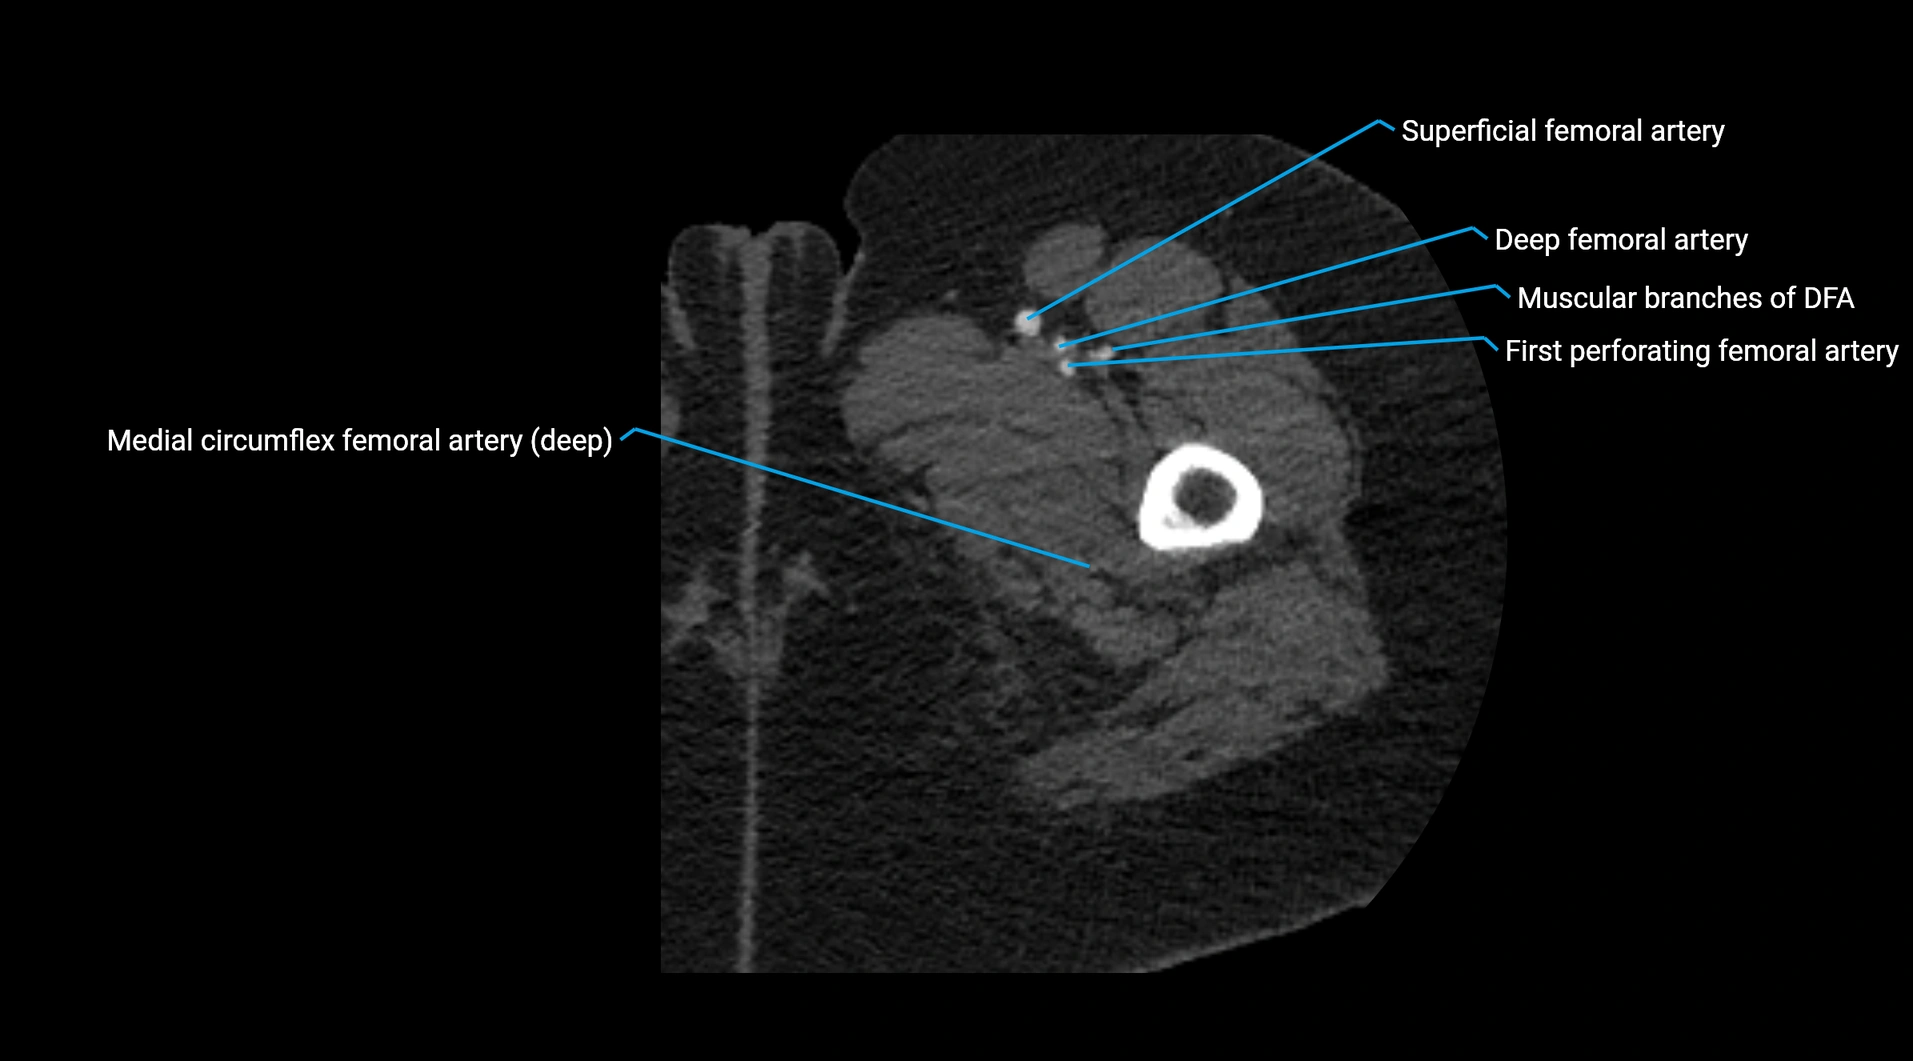

CT Appearance

Contrast-enhanced CT (CTA):

• Gold standard for abdominal aortic imaging

• Provides excellent detail of lumen, wall, aneurysm, thrombus, and branch vessels

• Multiplanar and 3D reconstructions help in aneurysm measurement, stent graft planning, and dissection evaluation

• Detects acute rupture, traumatic injury, or occlusion with high sensitivity

CT images

image